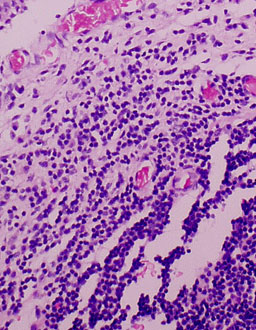

Cases